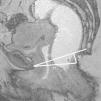

La valoración mediante RM de la relajación del suelo pélvico y los prolapsos se realiza mediante la clasificación HMO (línea H, línea M y prolapso de los órganos). Esta clasificación toma en consideración una serie de líneas de referencia sobre las que uniformizar los criterios de evaluación (fig. 4):

Línea pubococcígea (LPC). Desde el borde inferior de la sínfisis del pubis hasta la última articulación intercoccigea1,5-7,10. Representa el nivel por encima del cual se localizan las bases de los compartimentos anterior y medio en condiciones normales7.

Línea H. Desde la porción inferior de la sínfisis hasta la reflexión del músculo puborrectal en la pared posterior del recto. Indica el nivel y la extensión del suelo o hiato pélvico.

Línea M. Trazada perpendicularmente desde la LPC hasta el extremo posterior de la línea H.

Los prolapsos se dan en mayor o menor grado cuando los órganos pélvicos se muestran por debajo de la LPC5,9-11 (algunos autores proponen la línea H1), ya sea en reposo o durante el esfuerzo. El grado de relajación del hiato pélvico se obtiene por la valoración de 2 componentes diferenciados: su elongación y su descenso. La longitud de la línea H muestra la elongación anormal del hiato a partir de 6cm; la longitud de la línea M indica un descenso anormal a partir de 2cm (tablas 1 y 2).